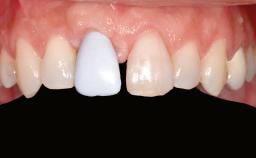

Iliac and Calvarial Bone Blocks for Onlay Grafting of a Severely Resorbed Edentulous Maxilla

A 45-year-old woman with a completely edentulous maxilla was referred to evaluate the possibility of rehabilitation with an implant-supported prosthesis. This patient was healthy and a non-smoker. She had been wearing a maxillary complete denture opposing a natural mandibular dentition since her twenties. This situation had resulted in progressive resorption of the alveolar ridge, repeatedly creating a need for relining the denture. Twenty years later, despite multiple adaptations and the use of “glues” the denture was unstable and causing the patient psychological and functional discomfort.

Prosthesis Type FDP

Defining Characteristics Fully edentulous upper jaw to be rehabilitated with an implant-borne fixed dental prosthesis